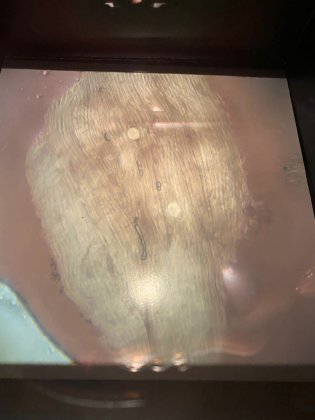

В госветслужбе Мурманской области рассказали, что при проведении исследования туши медведя, добытого охотником в Кольском районе, обнаружены личинки трихинелл. Трихинеллез — опасное для человека заболевание. Возбудитель - нематоды. На личиночной стадии развития они находятся в мышцах.

Половозрелая форма возбудителя паразитирует в тонком отделе кишечника. Человек может заболеть трихинеллезом при употреблении в пищу продуктов убоя зараженного животного. У людей трихинеллез, в том числе может привести и к тяжелому повреждению внутренних органов и центральной нервной системы.

Зараженная туша медведя была уничтожена — ее сожгли. Единственный способ убить трихинелл - варка и жарка. Засолка, сушка, копчение не уничтожают личинок гельминтов. Бесполезна и заморозка — личинки выдерживают холод до -40 °C.

Фото: vk.com/komvetmo